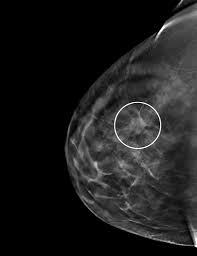

We'll show you breast cancer pictures to help you identify any physical traits of the condition. More importantly, the overlap can obscure small breast cancers. What does breast cancer look like on a mammogram? The outer edges of these cells look fuzzy or spiky (called spiculated). The doctor reading your mammogram will be looking for different types of breast changes, such as small white spots called calcifications, larger abnormal areas called masses, and other suspicious areas that could be signs of cancer.

3d Digital Mammogram Services Breast Tomosynthesis Buffalo Ny Windsong Radiology from windsongwny.com American cancer society, 9 oct 2017. In a normal breast, a mammogram shows normal skin dark grey fat and lighter grey breast tissue. Breast cancer can present either as an area of focal asymmetry or when advanced can even present as a new asymmetry in breast size. This is why you should always talk to your doctor if you notice an unexplained change in the size of a breast. Bright spots on a mammogram that look like potential tumors could turn out to be overlapping tissues or a blood vessel folding over on itself, friedewald said. Suspicious findings include clusters of tiny microcalcifications or a density/mass with irregular or spiculated margins. Finding breast lumps and seeing change in the size and shape. These deposits show up as tiny white spots on a mammogram, and there may be only one or two, or too many to count, says jay baker, md, a breast imaging specialist at the duke cancer center.

Any area that does not look like normal tissue is a possible cause for concern. Breast cancer can appear as a spiculated mass, cluster of tiny calcifications, smoothly marginated mass, area of subtle distortion or be invisible on. Several patterns of calcifications are seen with dcis, including: Any area that does not look like normal tissue is a possible cause for concern. A false positive is when a mammogram shows an abnormal area that looks like a cancer but turns out to be normal.

Most people assume that what doctors are looking for on a mammogram are lumps, dr. Diagnostic mammograms involve taking more views than screening mammograms. This decreases the overlap and makes it easier to see cancers. additionally, the combination of 2d and 3d mammogram imaging has been shown to reduce false positives that require a patient to return to the clinic for additional screening. Suspicious findings include clusters of tiny microcalcifications or a density/mass with irregular or spiculated margins. Most screening mammograms include two views of each breast taken from different angles. American cancer society, 9 oct 2017. A screening mammogram is performed at regular intervals to check for breast cancer in women who have no signs or symptoms of the disease. Images are displayed as a series of thin slices that can. A tumor that is benign, it is not a health problem and it may not grow or change shape. Several patterns of calcifications are seen with dcis, including: Even if you have a lump in only one breast, pictures will be taken of both breasts. A lump or tumor will show up as a focused white area on a mammogram. That makes it easy to detect abnormalities, which generally show up as white.